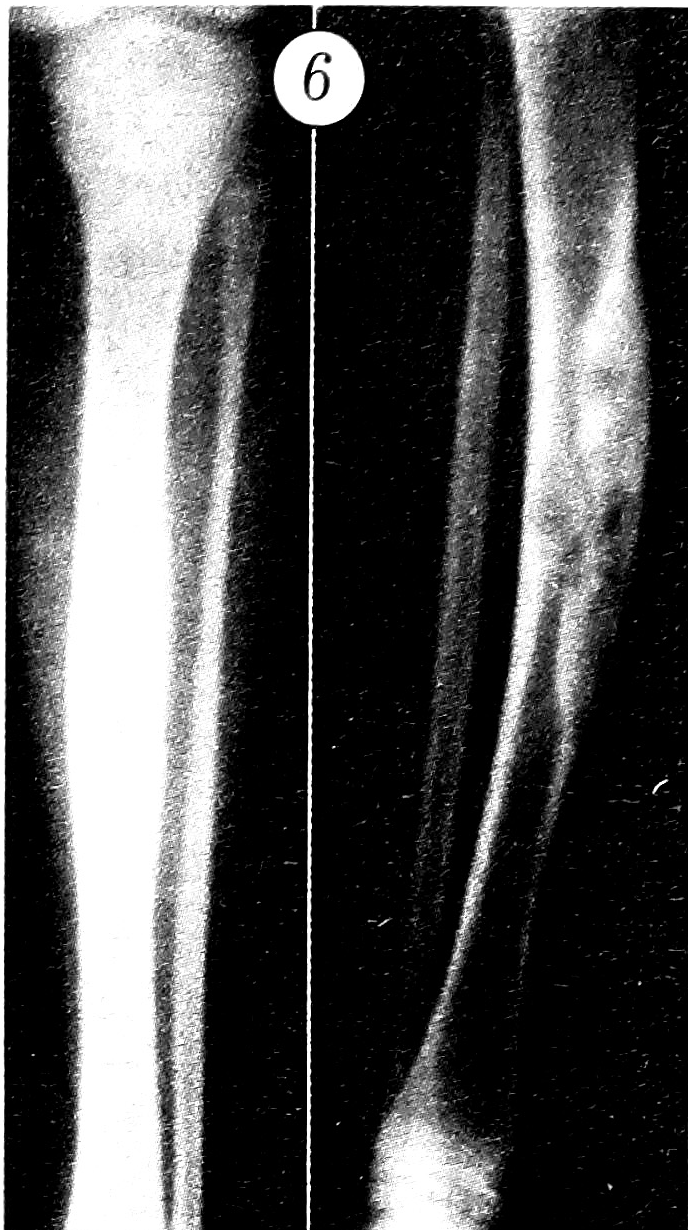

При фиброзной дисплазии патологический очаг в рентгеновском отображении также обнаруживает тропизм к кортикальному слою, однако очаги разрежения и «матового стекла», как правило, более крупные и имеют четкие контуры. Видны менее грубые перегородки между ними (рис. 5). Что касается рентгенологической картины адамантиномы, то в ней выявлены следующие отличия: патологический участок не имеет четкого тропизма к кортикальному слою и в равной степени поражает весь или почти весь поперечник кости. В очаге поражения выделяются центральные и периферические отделы без четких границ, различающиеся по своей структуре. Для центральных отделов характерны мелкие округлые очаги разрежения с четкими контурами, создающие своеобразный «пенистый» рисунок. В центральной части очага отсутствуют участки типа «матового стекла», однако по периферии основной массы опухоли отмечается структура, весьма напоминающая ОФД (рис. 6).

Рис. 5. Очаги разрежения и «матового стекла» в большой берцовой кости при фиброзной дисплазии.

Рис. 6. Очаг деструкции в большой берцовой кости при адамантиноме длинных костей.